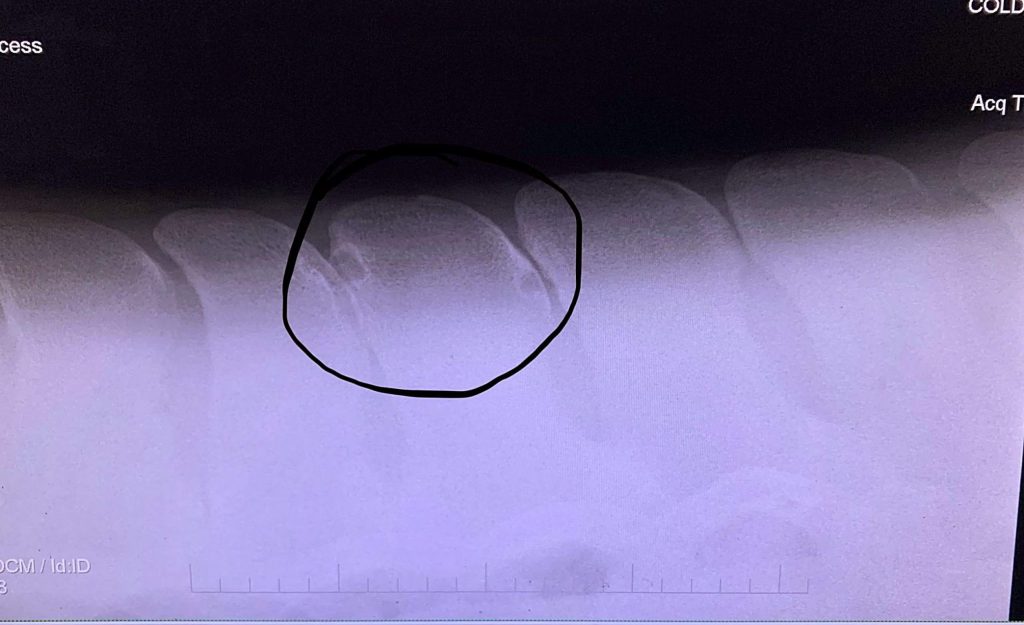

Photo provided by Bethann Coldiron

“Kissing spine involves one or more spaces between vertebrae that are either touching each other or overlapping,” Honnas said. “Nobody knows what causes it. A group of people in Europe think it is caused by horses being ridden too early, but I have started to x-ray some yearlings at a local farm and one of those already has it. So I don’t think it is caused by trauma. It could be genetic or just the way they are born.”

The only way to accurately diagnose kissing spine is through x-ray. Though the numbers have not yet been backed by clinical study, Honnas predicts 20 to 30 percent of horses have some sort of kissing spine. He once operated on a horse that required 10 vertebrae to be shaved down. However, just because an x-ray comes out positive for kissing spine that doesn’t always mean that the horse will exhibit pain. Honnas sees this frequently in pre-purchase exams.